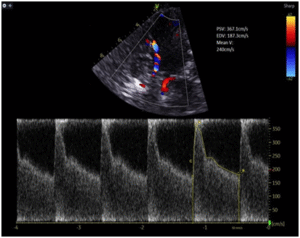

Case Description: A 53-year-old gentleman presented with a modified Fisher grade IV subarachnoid haemorrhage secondary to a ruptured anterior communicating artery (ACOM) aneurysm, treated with endovascular coiling. On post-bleed day 4, he developed symptomatic vasospasm. Despite maximal therapy including oral and intra-arterial nimodipine and hypertensive therapy in the intensive care unit, his neurological condition deteriorated. An ultrasound-guided left stellate ganglion block at C6/7 level was performed using 8 mL of 0.5% levobupivacaine with clonidine 75 mcg. The patient demonstrated immediate neurological improvement, with a reduction in left middle cerebral artery transcranial Doppler (TCD) mean velocity from 246 cm/s to 110 cm/s, without any procedural complications.